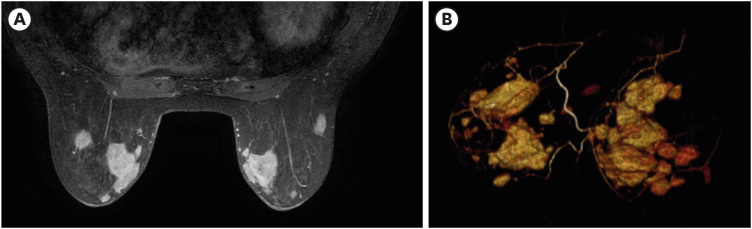

Erdheim-Chester disease (ECD) is a rare multisystem disorder characterized by mitogen-activated protein kinase (MAPK) pathway mutations. Herein, we present a unique case of ECD in a 79-year-old female with predominant breast nodules. Comprehensive imaging and histopathological evaluations confirmed the diagnosis. Mammography and ultrasonography revealed multiple hyperdense circumscribed nodules with coalescing masses and blurred margins. Core biopsy revealed infiltrating foamy cluster of differentiation (CD) 68+ and CD1a+ histiocytes. Because the tumor was negative for the BRAF V600E mutation, treatment with interferon-α was initiated. This case highlights the diagnostic challenges associated with ECD, the rarity of breast involvement, and the importance of considering ECD in the differential diagnosis of atypical breast lesions. Comprehensive imaging, histopathology, and genetic testing are essential for accurate diagnosis and treatment decision-making in ECD. Further research and awareness are required to improve recognition and management of this rare disease.